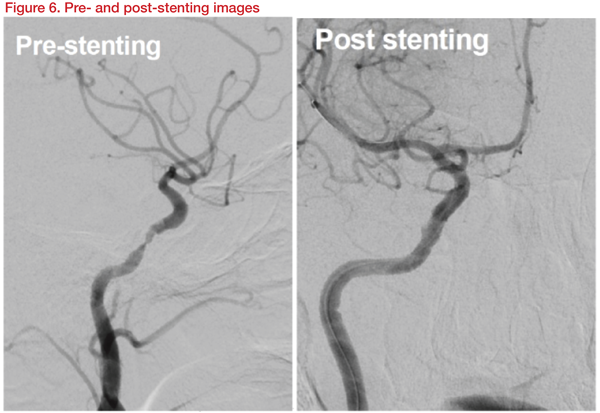

The patient was maintained with dual antiplatelet and high-dose statins. The patient again deteriorated to NIHSS score 13 later, after the IA thrombectomy. Definite restenosis was observed in cerebral angiography. Stenting was carried out with a Gateway balloon 3.5*15mm and Wingspan 4*20mm stent. After stenting, the patient improved to NIHSS Score 8 (Figure 6).